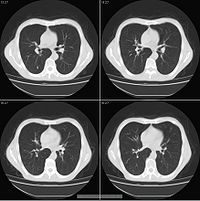

四、CT检查:贲门癌的CT检查能够了解贲门部与食管及周围脏器的关系。肿瘤侵润的情况、大小、部位、食管壁的增厚,上段食管扩张,淋巴结及远处脏器转移等情况。有利于贲门癌与食管癌的诊断和鉴别诊断。